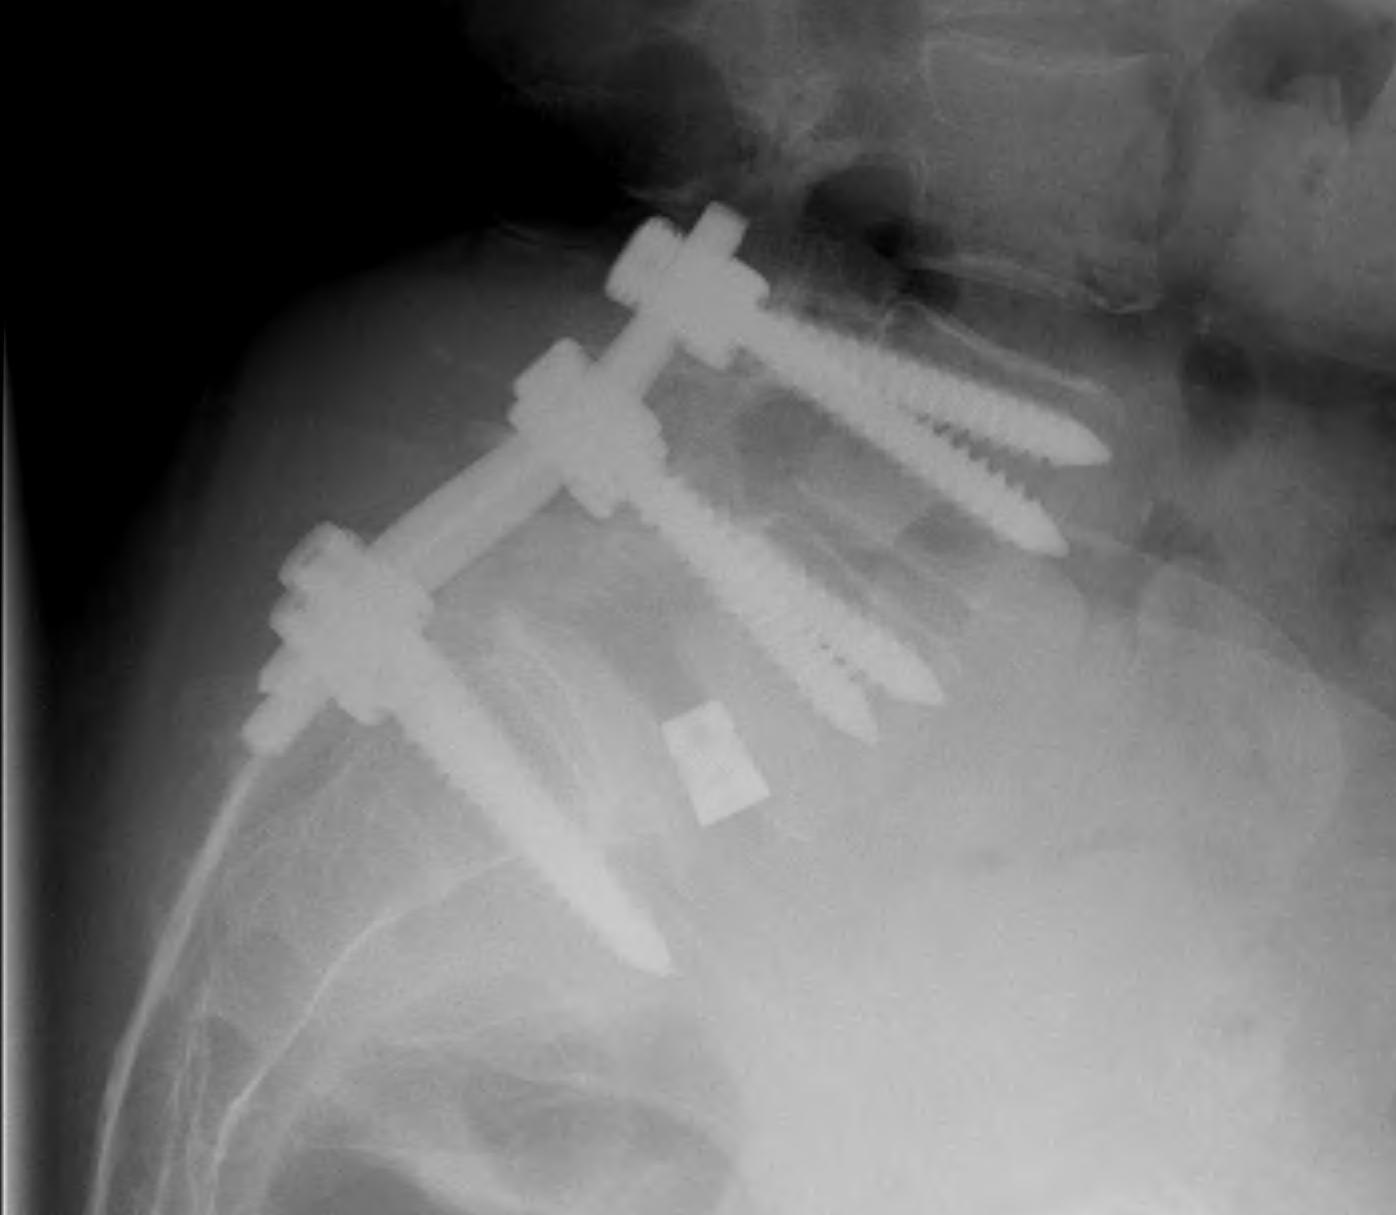

CT scan

Technique

- reverse gantry

Indication

- perform instead of obliques

- oblique x-rays have high radiation dose with little extra information compared with CT

Instrumented fusion in situ without reduction

Indications

- slip grade 1 or II

- grade III or IV with no sagittal malalignment

Levels instrumentation

- L5 / S1 grade I or II

- L4 / S1 grade III or IV

Options

1. Pedicle screw instrumentation

2. PLIF / interbody cage